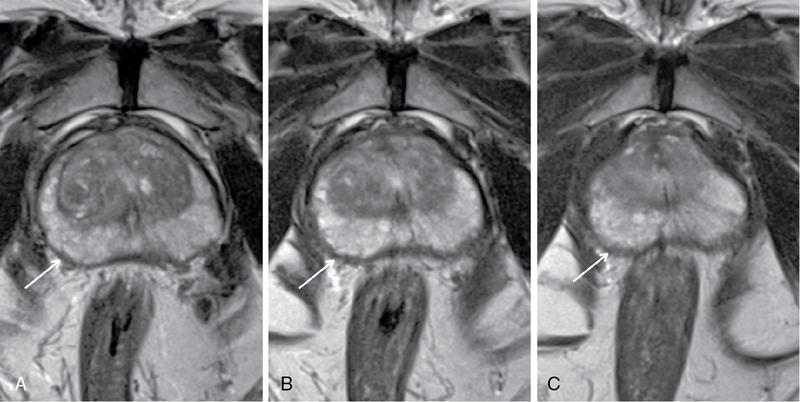

Karthik Ganesan, Disha Lokhandwala, Ujjwal Bhure, Jay Mehta Morphogenesis of the male genitourinary system is governed by the coherent interaction of three units, namely the Wolffian duct, urogenital sinus and foetal gonads. The Wolffian ducts are the embryonic precursors of the male internal genitalia, arising in the anterior intermediate mesoderm at 4 weeks of gestation. They elongate as a cord of cells that caudally extend to the urogenital sinus. Between 5 and 8 weeks of gestation, the urorectal septum divides the cloaca into a ventral compartment, which forms the urogenital sinus, and a dorsal compartment, which forms the rectum. The gonads form as epithelial thickenings on the ventromedial surface of the mesonephros and produce testosterone at 8 weeks of gestation, reaching a peak at 10–15 weeks. Under the effect of testosterone produced by the foetal testis, the prostate anlage forms at the tenth week of gestation. Precursor of the anlage begins with proliferation of solid epithelial buds from the epithelium of the urogenital septum into the adjoining mesenchyme in response to interaction of 5α-dihydrotestosterone with mesenchymal androgen receptors. As growth progresses, solid cords of epithelial cells are formed, growing into the mesenchyme in a specific three-dimensional arrangement (establishes the lobar divisions of the prostate gland). These solid cords develop a central lumen at birth and are lined by a layer of flat basal epithelium and a luminal layer of tall columnar secretory epithelium. Mesenchymal component forms the stroma, which has a large proportion of smooth muscle. Postnatally, the epithelial cords continue to arborize till puberty without any change in volume or glandular architecture. Although the foetal prostate has been described to have a histologically distinct peripheral zone (PZ) as early as 12 weeks of gestation, the mature zonal anatomy develops in concordance with the androgen surge at puberty. The most commonly utilized ultrasonographic technique for the evaluation of the prostate is via a suprapubic approach. The abdominal transducers used in this approach are relatively low frequency and while it offers the advantage of greater depth of penetration without intracavitary probe insertion; however, it does not depict the zonal anatomy and its chief application lies in volume estimation. Hence, transrectal ultrasonography (TRUS) completely outweighs the transabdominal approach in terms of depicting zonal anatomy, visualizing and localizing small lesions, demonstrating vascularity and performing biopsies. TRUS is performed using high frequency transducers (5–7.5 MHz) to optimize soft tissue resolution. An enema is administered 1 h prior to the examination to clear the field of insonation. Patient is positioned in left lateral decubitus, with knees bent toward the chest and ideally a digital rectal examination (DRE) is conducted prior to probe insertion. The transducer is first draped with a sterile barrier and lubricated, After insertion, the barrier is filled with 40–50 cc of water, making sure that no air enters. On completion, water is aspirated and the probe is withdrawn. The gland is initially scanned in the axial plane from the base to the apex, beginning at the level of the seminal vesicles, and the probe is gradually withdrawn to view the entire glandular parenchyma in axial sections up to its caudal aspect. This approach allows a cursory evaluation of glandular symmetry as both halves of the prostate can be evaluated simultaneously. Subsequently, sagittal views are acquired by rotating the probe across the transverse span of the gland, demonstrating the seminal vesicles, midline gland (visualizing both the apex and the base), with sequential scanning up to the contralateral margin of the gland. Sonographically, the prostatic capsule is seen as a smooth well-delineated, hyperechoic structure. With the newer ultrasound systems, the zonal anatomy can be delineated by TRUS; PZ appears echogenic relative to the central zone (CZ) and the transition zone (TZ), which are hypoechoic in juxtaposition (Fig. 11.12.1). Anterolaterally, the preprostatic venous plexuses are seen as anechoic tubular structures with intervening echogenic preprostatic fatty tissue. Glandular volume is estimated using an ellipsoid formula by obtaining the maximum anteroposterior, superoinferior and transverse dimensions and multiplying their product by π/6. Colour Doppler imaging is utilized to illustrate vascularity, as majority of the normal prostatic tissue (excluding the neurovascular bundles [NVBs] and pericapsular and periurethral regions) has symmetrical but sparse flow and an increased microvessel density raises the suspicion of prostatic carcinoma. However, the appearances of prostatic carcinoma can be variable on colour Doppler imaging, ranging from focal increase in vascularity around a nodule to an asymmetric increase in size and number of vessels on the affected side and conventional Doppler has found to elevate specificity by about 5%–10%. Additionally, Doppler imaging has also demonstrated some utility in distinguishing fibrotic tissue from local recurrence. However, vessels supplying cancerous tissue are of the order of 10–50 μm, which is well below the 1-mm resolution limit of conventional Doppler techniques. Contrast-enhanced colour Doppler imaging overcomes this limitation and facilitates imaging of microvessels, using intravenously administered microbubbles (less than 10 μm diameter) of an inert gas (sulphur hexafluoride) with a lipid or galactose shell, allowing quantification of blood flow in the cancerous microvessels. Additionally, these microbubbles act as vascular tracers and by monitoring the passage of a bolus injection through the tissue of interest, time–intensity curves are created. This permits the formulation of functional indices, including bolus arrival time, time to peak intensity, area under the curve and wash-in/wash-out curves. These indices can further extrapolate functional images, on a pixel-by-pixel basis, overlaid on grey-scale images. Quantitative methods to demonstrate perfusion are based on the destruction of microbubbles by high-power ultrasound pulses, and then observing the rate of microbubble replenishment in the field of interest to calculate flow rate. Halpern et al. utilized contrast-enhanced ultrasound and intermittent harmonic imaging with power Doppler, and exhibited an increment in sensitivity from 38% to 65% with a specificity of 80% in prostate cancer detection. Cadence contrast pulse sequencing (CPS) is a low-power multipulse imaging technique utilizing pulses with variable amplitudes and phases followed by a summation of the resulting echoes, permitting tissue suppression, allowing detection of even a small amount of contrast agents retained in the tissues. Real time elastosonography evaluates and quantifies tissue stiffness (Young’s modulus) by measuring strain under an applied stress (transducer compression) and maps areas of variable stiffness in colour-coded and grey-scale images simultaneously and shows potential in improving prostatic carcinoma detection. In a study comparing elastography and T2-weighted (T2-w) endorectal magnetic resonance imaging (MRI), similar sensitivity rates and negative predictive values (NPVs) were attained in the detection of prostatic carcinoma. Prostate gland is an inverted cone-shaped subperitoneal retropubic gland, with its base located rostrally and apex located caudally. The base is attached to the bladder neck and the apex sits on the urogenital diaphragm and abuts the medial surface of the levator ani muscles, namely the pubourethralis portion, which is separated from the inferolateral surfaces of the gland on either side by the prostatic venous plexus. Normal prostate gland measures approximately 4 × 3 × 3 cm, 15–20 g in weight, with a median volume of 11.5 mL (range, 1.6–20.6) in patients between 21 and 25 years and a median volume of 39.6 mL (range, 13–169.8) in patients between 38 and 83 years. The first comprehensive publication describing the anatomical subdivision of the prostate gland was in 1912 by Lowsley, based entirely on the embryonic glandular morphology at a series of gestational age groups. The budding prostatic ducts were seen to proliferate in five distinct clusters from the primitive urogenital sinus, which formed the basis of its lobar subdivision. It was divided into a ventral lobe (anterior to the urethra), two lateral lobes (lateral to the ejaculatory ducts), a posterior lobe (between the ejaculatory ducts) and a middle lobe (above the ejaculatory ducts). This classification had several shortcomings, the foremost being inclusion of only the embryonic prostate during its conception. Frank highlighted these aspects in 1953 and stated that no definite lobar boundaries exist in the adult prostate and further criticized the exclusion of periurethral glands (inner gland), identifying them as the sole site of origin of benign prostatic hyperplasia (BPH). The chief drawback of all research prior to 1968 was the lack of a concrete histological basis to support the seemingly arbitrary subdivision. McNeal was the first to ascertain histological heterogeneity within the glandular tissue and used it as the basis of his well-acclaimed prostatic zonal classification. The zonal anatomy of the prostate gland conceived by McNeal divided the gland into four distinct zones, namely the TZ, PZ, anterior fibromuscular zone (AFMZ) and the CZ (Fig. 11.12.2). McNeal used the plane of the distal urethra to describe the zonal relationships and divide the gland broadly into three parts, namely the base, midgland and the apex (Fig. 11.12.3). The improved understanding of the prostate anatomy coincided with the development of MRI in the late 1980s, which could depict the zonal anatomy, unlike ultrasonography (USG) or computed tomography (CT). Patterns of ductal growth and radiation from the prostatic urethra form the basis of the zonal anatomy of the gland. Ducts arising from the proximal urethral segment grow towards the urinary bladder. Tiny ducts which are confined by the preprostatic sphincter form the small periurethral gland, whereas ducts which develop distal to the lower border of the preprostatic sphincter extend laterally and then anteromedially to form the TZ. Ducts arising from the verumontanum in the vicinity of the ejaculatory duct orifices and are directed towards the base along the course of the ejaculatory ducts form the CZ, whereas ducts which arise from the lateral recess of the posterior urethral wall of the verumontanum and distal urethra radiate laterally to form the PZ and rostrally posterior to the CZ at the base of the gland. PZ is the dominant glandular component of the prostate gland comprising approximately 70% of the glandular tissue. On T2-w images, the normal PZ has a high T2 signal intensity (SI), owing to the abundant ductal and acinar elements with sparsely interwoven smooth muscle, and can broadly divided into three sections as per the sector map in Prostate Imaging Reporting and Data System Version 2.1 (PI-RADS v2.1), namely posterior medial, posterior lateral and anterior sections (Fig. 11.12.4). At the apex, the anterior sections have a horn-like morphology, curving anteromedially, to nearly encircle the urethra and abut the AFMZ. At the midgland level, the PZ comprises the posterior, both lateral and the anterolateral parts of the gland. At the base, the PZ is located posterior and superior to the CZ and TZ. CZ is an ovoid-shaped structure at the base of the gland, comprising approximately 25% of the glandular tissue, with its apex located at the verumontanum, surrounding the ejaculatory ducts. Beyond age 35, volume of the CZ starts to gradually diminish, as well as the CZ is compressed by the enlarged TZ. In the initial MR studies of prostate, the CZ could not be easily delineated from the TZ. Vargas et al. demonstrated in a population with a mean age of 60 years undergoing MR for prostate cancer assessment, the CZ was visible in 81%–84% of patients. Hansford et al. identified the CZ in 92%–93% of patients on T2-w images and 78%–88% of patients on apparent diffusion coefficient (ADC) maps. Histologically, substantial differences exist between the CZ and PZ, which reflect in the differential appearance on T2-w imaging. These differences are probably attributable to the differential origin, as the CZ is derived from the Wolffian duct, and the PZ and TZ are derived from the urogenital sinus. In the CZ, the acini appear larger and more irregular, with numerous epithelial covered ridges or septa project from the walls of the acini into the lumen, forming a characteristic Roman bridge architecture and intraglandular lacuna, with a prominent basal layer, crowded epithelial cells with granular eosinophilic cytoplasm, decreased luminal fluid and compact stroma. PI-RADS v2 has discouraged the use of the term central gland, as it is not reflective of zonal anatomy or reported on pathologic specimens. CZ demonstrates homogeneously low signal on the T2-w images and ADC maps and can, therefore, mimic prostate cancers. CZ is best identified on the coronal plane T2-w images paralleling the plane of the distal urethra, and appears as a symmetric paramedic paired structures surrounding the ejaculatory ducts from the base of the gland to the verumontanum (Fig. 11.12.5). TZ comprises approximately 5% of the glandular tissue of the prostate. On T2-w images, the TZ normally appears as a homogeneously hypointense structure surrounding the proximal urethra at the base and the midgland level; however, it can also demonstrate inconsistent SI, depending on the relative proportion of glandular and stromal elements (Fig. 11.12.6). Glandular hyperplasia produces higher SI (dominance of acinar elements and secretions), while stromal hyperplasia exhibits lower SI (dominance of muscular and fibrous elements). The TZ is easily demarcated from the PZ by a thick homogeneously low T2 signal surgical capsule, which becomes pronounced in BPH. With increasing age, the TZ demonstrates variegated signal on the T2-w images and ADC maps, due to differential growth of the stromal and glandular elements. AFMZ is a nonglandular muscular tissue that drapes the anterior surface of the gland, superiorly blending into the smooth muscles of the bladder neck and inferiorly extending to the prostatic urethra at the glandular apex. AFMZ is comprised of smooth muscles, which blends with the smooth muscle fibres surrounding the urethra, and rostrally merges with the bladder neck and preprostatic sphincter. High smooth muscle content of the AFMZ is responsible for the MR signature, where in it appears markedly hypointense on the T2-w images and ADC maps, and hypoenhances on the multiphase contrast series (Fig. 11.12.7). With the advancing age, temporal reduction in the size of the AFMZ is noted due to the compressive effects of the BPH. Capsule surrounds the prostate gland, anteriorly merging with the AFMZ anteriorly. Two discrete defects are identified in the prostate capsule, at the base of gland where the ejaculatory ducts enter the prostate and at the apex where in the stroma blends with the sphincter. The capsule is perforated along the anterolateral aspect by multiple vessels and nerves. The capsule appears as a thin dark rim surrounding the gland on the T2-w images and may reveal delayed enhancement on the postcontrast images (Fig. 11.12.8). Primary goal of radical prostatectomy (RP) is to achieve oncologic efficacy, both in terms of short-term and long-term clinical outcomes. However, as the majority of prostate cancers have an indolent clinical course, preservation of function in terms of continence and potency is equally important, and the key to this is a keen understanding of the fascial anatomy and neuroanatomy of the prostate gland. Fascial anatomy of the prostate gland is anatomically complex and poorly understood, and a thorough understanding of the interfacial planes is crucial to avoid mechanical or thermal injury to the NVBs. Periprostatic fascia comprises of a condensation of layers of connective tissue that encapsulate the gland and suspend it from anterior pelvic wall via puboprostatic ligaments. Laterally, the visceral and parietal endopelvic fascial layers fuse to form the fascial tendinous arch. Periprostatic fascia covers the prostate gland and capsule, comprises of two fascial layers, including an inner layer (prostatic fascia) and an outer layer (levator ani fascia), with thin interfascial planes separating these fascia from one another and the prostate capsule. Posteriorly, a continuous fascial layer known as Denonvilliers’ fascia covers the prostate and seminal vesicles. Distribution of periprostatic nerves is highly variable, with growing evidence of nerves both along the dorsolateral and ventrolateral surfaces of the prostate gland. Most of the periprostatic nerves are found posterolaterally; however, a significant portion of the nerves are located ventrally as seen by Eichelberg et al. (21.5%–28.5%) and Lee et al. (19.9%–22.8%). Although anatomic studies have confirmed the presence of ventrolateral periprostatic nerves, the exact clinical importance and functionality of these nerve fibres has not been proven. The cavernous nerves are situated posterolaterally and are the basis of nerve-sparing RP procedure proposed by Walsh and Donker. Unlike the initial theory of Walsh and Donker, few papers have proposed that the nerves are diffusely scattered along the surface of the gland in the form of a curtain or spray-like arrangement without clear bundle formation. Kourambas et al. assessed the precise relationship of the NVBs and cavernous nerves to Denonvilliers’ fascia and proposed that the nerves were not restricted posterolaterally, but were rather diffusely scattered within the fascia extending up to the midline (Lunacek et al., Takenaka et al.). On the basis of more diffuse arrangement of the periprostatic nerves, surgical techniques have been modified, resulting in a more anterior dissection called the ‘curtain dissection technique’ or alternatively a ‘superveil’ technique to preserve the NVBs within the lateral prostatic fascia. The NVB lies within areolar connective tissue surrounding the gland, which separates the capsule from the periprostatic fascia and provides a plane of dissection during nerve-sparing prostatectomy. Prostate gland is supplied and drained by periprostatic vessels, which also supply and drain the penis. Arterial supply of the gland is highly variable and is typically from branches of the internal pudendal artery, which course inferior to the gland prior to supplying the penile cavernosal tissue. Off late, these vessels have gained prominence in radiation-induced erectile dysfunction (ED) (potential vasculopathy), which have led to the development of newer vessel-sparing radiotherapy techniques. Further, with the advent of prostate arterial embolization in benign prostatic hypertrophy (BPH), the vascular supply of the gland is becoming increasingly vital to understand. Gland drains into the obturator, internal iliac, external iliac, common iliac and presacral lymph nodes. Dorsal venous complex is identified immediately ventral to the gland and also drains the penis. Periprostatic nodes are uncommon, are usually discovered near the base of the gland, and are only occasionally seen on MRI. Urethra is the principal anatomic reference point in the prostate gland. Urethra can be divided into a proximal segment and a distal segment, the point of differentiation being located at the verumontanum wherein the urethra makes an approximately 35-degree angulation. The angulation is highly variable and is further affected by the growth of the TZ. On MRI, the distal segment is more conspicuous vis-à-vis the proximal segment and appears a hyperintense core surrounded by a low signal rim on T2-w images. Preprostatic sphincter encases the proximal urethra from the base of the gland to the base of the verumontanum and merges with the AFMZ anteriorly. Verumontanum appears hyperintense on the T2-w images, lies within the distal urethral segment, beyond which the distal urethral segment is partially encircled by striated muscles which blend with the external sphincter beyond the apex of the gland. External sphincter is located distal to the apex is incomplete posteriorly and is anchored into the PZ and surrounds the membranous urethra. Damage to the external sphincter during RP or transurethral resection of the prostate (TURP) may lead to urinary incontinence. Seminal vesicles are paired structures identified posterosuperior to the base of the prostate gland, which appear as convoluted fluid-filled structures. Due to the high fluid content within the normal seminal vesicles, these structures appear as paired structures with intermediate signal walls surrounding a hyperintense core on T2-w images (Fig. 11.12.9). Vas deferens are paired structures located rostral to the base of the gland and anteromedial to the seminal vesicles and appear as cord-like structures with variable signal on the T2-w images. Duct of the seminal vesicle and vas deferens unite in the posterior aspect of the base of the gland to form the ejaculatory duct, which courses caudally to the verumontanum along the plane of the distal urethra, and drain into the orifices in the midconvexity of the verumontanum. Prostate-specific antigen (PSA) is a serine protease, secreted by epithelial cells of the prostate gland and has been found in normal, benign and malignant prostatic tissues. Traces of PSA have also been isolated from endometrial tissue, breast tissue, adrenal neoplasms and renal cell carcinomas; however, for all clinical purposes, PSA is considered as an organ-specific biomarker. Papsidero first demonstrated and quantified serum PSA, which steered the epoch of prostate cancer screening and early detection of prostatic carcinoma. Subsequent studies showed that PSA screening often led to overdiagnosis of low-grade prostate cancers, with no survival difference between the PSA screened and nonscreened groups. Additionally, PSA levels were found to be elevated in a spectrum of prostatic pathologies apart from carcinoma, including prostatitis and benign hyperplasia. The likelihood of overdiagnosis coupled with the lack of specificity set grounds for the longstanding PSA controversy. Did the benefits of screening outweigh the risks of overtreatment? To elevate the specificity of serum PSA testing, a plethora of indices were devised, including free PSA and total PSA, free-to-total PSA (f/t PSA) ratio, age-specific PSA, PSA velocity (PSA-V) and PSA density (PSAD). Serum PSA exists in three forms; the major form (approximately 75%) is bound to alpha-1-antichymotrypsin, followed by free PSA (constituting 5%–50% of serum PSA). The third form (PSA bound to alpha-2-macroglobulin) is not clinically relevant and cannot be detected by any commercial test. A study by Stenman et al. established that a higher proportion of bound PSA and hence a lower ratio of f/t PSA is associated with prostate cancer. Conversely, free PSA can be utilized during follow-up for men with an initial negative biopsy result, wherein declining free PSA with a persistently elevated total PSA would raise suspicion of a neoplastic aetiology. As per the ACS guidelines (Table 11.12.1) for early detection of prostate cancer, men with a 10-year life expectancy or higher should have the opportunity to make an informed (regarding benefits, risks and uncertainties associated with PSA screening) decision for serum PSA testing, with or without DRE. For those who choose to undergo PSA screening, subsequent screening interval is determined on the basis of baseline PSA value. For values below 2.5 ng/mL, screening interval can be extended to 2 years and for PSA between 2.5 ng/mL and 4 ng/mL, an individualized approach is adopted following risk assessment to recommend either further referral or screening on a yearly basis. A PSA level of 4 ng/mL or higher warrants referral for further evaluation or biopsy, for men at average risk for prostate cancer. Although age-specific PSA (Table 11.12.2) is not a component of the ACS guidelines, it is considered as a beneficial parameter in determining the need for biopsy. As there is an expected rise in PSA values with age, setting a lower cut-off value for younger men would increase the sensitivity of detecting organ confined cancers and a higher value in older men would increase specificity. aThere is no proven rationale for using a single PSA-V threshold value. PSA screening guidelines for treated localized prostate cancers are variable and the definition of biochemical (PSA) recurrence remains debatable. Due to this inconsistency, the Prostate Cancer Guidelines Update Panel recommended a standard definition for biochemical recurrence (BCR) after RP and set a cut-off serum PSA (acquired between 6 weeks and 3 months of surgery) of 0.2 ng/mL or greater, along with a second confirmatory PSA. While there is a significant fall in PSA values after RP and a single raised PSA is sufficient to raise suspicion of recurrence, postradiotherapy recurrence requires a rising trend rather than a single cut-off value. The ASTRO Consensus Panel defined postradiotherapy prostate cancer recurrence as three consecutive raises in PSA values after a baseline has been reached. A hiatus in this definition was that no specific time interval between consecutive increases in PSA was determined. In addition to its utility as a screening tool, PSA is also a good prognosticator when used in conjunction with biopsy Gleason score and clinical T-stage, and several pretreatment prostate cancer risk stratification systems are based on these indices. D’Amico et al. proposed a three-group risk stratification system in 1998, which categorized nonmetastatic (M0) carcinomas as low risk, intermediate risk and high risk. Low-risk prostate cancer was defined as 1992 AJCC T1/T2a, PSA ≤10 ng/mL and Gleason score ≤6. Intermediate-risk prostate cancer was defined as 1992 AJCC T2b, and/or PSA 10–20 ng/mL and/or Gleason 7 disease. High-risk disease included any one of the following: 1992 AJCC ≥T2c, PSA >20 ng/mL or Gleason 8–10 disease. In 2001, the GUROC published the results of a consensus meeting which categorized the groups as follows: low risk – 1997 AJCC T1–T2a, PSA ≤10 ng/mL and Gleason ≤6; intermediate risk – 1997 AJCC T1–T2, PSA ≤20 ng/mL and Gleason ≤7 not otherwise low risk and high risk – 1997 AJCC T3–T4 or PSA >20 ng/mL or Gleason 8–10. In due course, newer classification systems have been developed (Table 11.12.3), including the National Comprehensive Cancer Network (NCCN, USA), National Institute for Health and Clinical Excellence (NICE, UK), European Society of Medical Oncology (ESMO), American Urological Association (AUA) and the European Association of Urology (EAU). The NCCN guidelines also incorporate very low-risk (T1c, and Gleason score ≤6, PSA ≤10 ng/mL, <3 positive biopsy cores each ≤50% involved and PSAD of <0.15 ng/mL/g) and very high-risk (T3b–T4) categories. AUA, American Urological Association; EAU, European Association of Urology; GUROC, Genitourinary Radiation Oncologists of Canada; NICE, National Institute for Health and Clinical Excellence; CAPSURE, Cancer of the Prostate Strategic Urologic Research Endeavour; NCCN, National Comprehensive Cancer Network; ESMO, European Association of Urology; T, T-stage; GS, Gleason score; PSA, prostate-specific antigen. Note: Use of the 1997 TNM staging system (T2a one lobe involvement, T2b two lobes involvement, no T2c category). PSA, DRE and TRUS form the diagnostic triad for prostatic carcinoma. It has been well established that manipulations of the prostate gland, including prostatic massage, cystoscopy and perineal biopsy cause a potential increase in serum PSA levels. This raised the question of TRUS affecting PSA levels and it was found to cause a very small rise in PSA only in patients with prostatitis. The effect of DRE on serum PSA levels is also controversial, while some studies found a transient increase in PSA, others found no significant rise in PSA levels after DRE. Therefore, it is advisable to obtain blood samples for PSA testing either prior to DRE and TRUS or after at least 7 days. PSA-V refers to the change in PSA over time using serial measurements. Ideally, at least three consecutive measurements over at least 18–24 months should be used. Carter et al. first defined PSA-V and found that a value of 0.75 ng/mL per year or greater was indicative of carcinoma with a high sensitivity and specificity. Consequently, several studies disproved a definite relationship between PSA-V and prostate cancer, stating that there was no rationale behind a single threshold value for PSA-V. Further, it was found that calculating PSA-V was arduous and while elevated PSA values on serial examinations should raise alarm, there was no added benefit of formally calculating PSA-V. As per NCCN guidelines, the PSA-V cut-off should be based on the initial PSA value with a PSA-V of 0.35 ng/mL/y, when the PSA is ≤2.5 ng/mL and 0.75 ng/mL/y, when the PSA is 4–10 ng/mL PSAD was developed in order to correlate prostate volume and PSA values. The basis of PSAD was that cancer cells produce more PSA per unit volume than normal cells. It is calculated as PSA value divided by the prostate volume as determined by TRUS. This reliance on TRUS leads to interobserver variability and hence PSAD values would differ with the performing sonologist. The chief utility of PSAD is in the diagnostic grey zone of PSA values between 4 and 10 ng/mL and the most commonly used cut-off value is 0.15 ng/mL/cc. However, more recent studies have shown that a value of 0.08 ng/mL/cc has an NPV of 95% in predicting prostate cancer. Additionally, PSAD in conjunction with MRI (PI-RADS score) has proved to be a reliable prognosticator for Gleason score upgrading. The most significant application being avoiding unnecessary biopsies as PI-RADS scores of 1–3 along with PSAD values <0.15 ng/mL/cc showed no Gleason score upgrading on repeat biopsies. In summary, most guidelines recommend shared decision-making for screening of prostate cancer. Limited testing should be conducted in men with low PSA values and a lower life expectancy. The aim should be to overcome challenges posed by the inherent nonspecific nature of serum PSA and reduce superfluous testing, unwarranted biopsies and overdiagnosis. Reliance on parameters like PSA-V that do not have a proven scientific basis is avoidable. Whereas applications of PSA like PSAD along with MRI can greatly reduce patient burden by avoiding follow-up biopsies. Lastly, PSA has no role in assignment of a PI-RADS category, which is based on multiparametric MRI (mpMRI) findings alone. Several ‘novel biomarkers’ are now being developed which are more specific in detecting high-grade prostatic carcinomas. Other human kallikrein proteins have been identified, as prostate cancer biomarkers, of which, human kallikrein 2 (hK2) has shown a high specificity. While hK2 and PSA have an overlapping primary structure, malignant cells express hK2 to a higher degree than benign epithelial cells, particularly in aggressive cancers. Engrailed-2 (EN2) is an HOX gene family transcription factor seen exclusively in malignant prostate tissue, with a reported sensitivity and specificity of 66% and 88%, respectively. Annexin A3 is a calcium-binding protein measured in urine samples following prostatic massage, potentially reducing unnecessary biopsy in men with a PSA of 2–10 ng/mL. However, extensive prospective evaluation of these biomarkers is necessary to replace PSA testing in clinical practice. Positron emission tomography (PET)/CT has evolved over the last two decades to make a paradigm shift in the field of imaging, moving from morphological imaging to molecular level and completely changing the approach to how we view the disease. Though the main workhorse tracer in the field of PET/CT is 18-fluorine-fluorodeoxyglucose (18F-FDG), it has limitations with regard to prostate cancer, especially in indolent or well-differentiated ones. However, that void has been filled up by the new kid on the block and that is prostate-specific membrane antigen (PSMA)-based radiotracer. PSMA is a type II transmembrane protein with intracellular (19 amino acids), transmembrane (24 amino acids) and extracellular (707 amino acids) domains, which functions biochemically as a glutamate carboxypeptidase. After a ligand binds to PSMA, internalization occurs and it is either retained in lysosomal compartments or released into the cytoplasm. PSMA expression and localization in the normal human prostate is associated with cytoplasm and apical side of the epithelium surrounding prostatic ducts but not basal epithelium and neuroendocrine or stromal cells. Neoplastic transformation of prostate tissue results in the transfer of PSMA from the apical membrane to the luminal surface of the ducts. PSMA is an ideal target for molecular imaging of prostate cancer as its expression is significantly upregulated in prostatic carcinoma cells compared to benign prostatic tissue, in density (100 to 1000 times) as well as activity (8 to 10 times). PSMA expression increases with increase in Gleason score, stage and grade of tumour, with further increased expression with transition to androgen-independent/castration-resistant prostate cancer. PSMA-binding analogues, because of their high sensitivity and specificity, possess precise imaging characteristics required for critical decisions in the management of prostate cancer (PCa). The most commonly used PSMA radiotracer is 68Gallium-PSMA-11, followed by 18F-PSMA. The availability of 18F-labelled PSMA radiopharmaceutical has helped to advance the reach of PSMA PET imaging to wider locations owing to higher available amount of the radiotracer due to its production from a cyclotron, compared to 68Ga-PSMA which is eluted from individual in-house generator. Additional benefit is accrued with excellent image quality owing to optimized radiotracer doses, higher imaging statistics and favourable decay properties of 18F radioisotope. The normal physiological biodistribution of PSMA-based radiotracers is seen in lacrimal and salivary glands, liver, spleen, kidneys and intestine. Physiological activity is also seen in celiac and cervicothoracic ganglia. Unbound PSMA radiotracer is excreted by the kidneys into the urinary bladder. PSMA PET/CT has established roles of varying degrees in the imaging of different aspects of prostate cancer including primary diagnosis, staging, BCR after primary prostate cancer treatment (prostatectomy), identification and significance of oligometastasis, restaging and treatment response assessment and monitoring. PSMA PET/CT is useful at the stage of diagnosis in that subset of patients with tumour-negative biopsy samples, by contributing the useful molecular information to mpMRI, helping to precisely delineate suspicious lesions for targeted biopsies. In intermediate-risk to high-risk primary prostate cancer patients, PSMA-based imaging has shown improvement in detection of metastatic disease compared to the CT and mpMRI, which has led to reduced demand and dependence on additional cross-sectional imaging or bone scintigraphy. Furthermore, PSMA PET/CT has also established its clear advantage over conventional imaging in patients with biochemically recurrent prostate cancer with improved and increased detection of metastatic sites even at low serum PSA values. As it happens in cancer, biopsy is the standard of diagnosis and likewise in PCa, it is the multicore biopsy, which is the gold standard. However, because of its size, location, approach and sensitive and delicate nature, yield and accuracy can often be restricted, especially in inexperienced hands. The diagnostic yield of biopsy can go down as low as 40% and false negative (FN) rate can climb as high as 25%–30%. PSMA overexpression follows high-grade PCa cells and increases with Gleason score. In normal prostate tissue, PSMA to PSA ratio is about 1, which decreases in BPH, increases in primary PCa cells, further increases with intratumoural angiogenesis, higher in metastatic lesions than in primary PCa cells and further upregulated in castration-resistant situation. In a study by Litwin and Tan in 2017, the FN rate of multicore biopsy was around 21%–28% and about 15% of the cases were undergraded vis-à-vis final prostatectomy results. While the diagnostic accuracy of random multicore biopsy was around 76.3%, that of 68Ga-PSMA PET/CT was upward in the range of 85.5%. The role of PSMA PET/CT in the primary/initial diagnosis of prostate cancer is generally limited to clinically intermediate-risk to high-risk patients with negative biopsy or reluctance to biopsy or noncooperation or nonfeasibility and for confirmation and staging in clinically high-risk patients. In low-risk patients, metastatic spread is very unlikely and hence it is a relative indication at the time of initial diagnosis in low-risk patients. And, its role in screening is variable and debatable (Fig. 11.12.10). Staging is crucial as it has considerable influence on deciding further line of management and treatment choices, which includes RP, radiotherapy or palliative systemic treatment, deciding on the extent of the pelvic nodal dissection during surgery, planning the radiotherapy field and consideration of multimodal therapy. Accurate staging helps to make the most appropriate choice of treatment modality (Fig. 11.12.11). In a meta-analysis of five studies with histopathology as gold standard, which included 216 patients, the per-lesion sensitivity of 68Ga-PSMA PET/CT ranged from 33% to 92% (33% value being an outlier due to the retrospective analysis based only on the reports, in absence of the images) with higher specificity of 82%–100%. For T-staging, PSMA PET/CT showed a significantly higher tumour detection rate of 92% vis-à-vis 66% with MR alone. In regard with N-staging, the majority of metastatic nodes from prostate cancer are small subcentimetre-sized, less than 8 mm, which are overlooked, missed or inconclusive on morphological imaging (CT and MRI) (falling below size criteria for morphological imaging). Accurate N-staging is important because lymph node involvement is a critical prognostic factor in cancer management, and precise pelvic nodal clearance could be curative and could make a difference in treatment success and long-term outcome in prostate cancer (Fig. 11.12.12). Also, accurate prediction of pelvic nodal metastases may spare nodal dissection, shorten surgical time and in turn help to reduce undesirable complications. In one study from 2016 involving 130 patients with intermediate-risk to high-risk prostate cancer, the metastatic nodal detection rate by 68Ga-PSMA PET was around 66% compared to 44% with MRI. PSMA PET has shown superior predictive value for surgical response over Gleason score, pT stage and PSA (at the time of imaging). In a literature overview by Luiting et al. in 2019 involving 9 retrospective and 2 prospective studies, the specificity of PSMA PET/CT in detection of pelvic nodal metastases before initial treatment reached as high as 80%–100%. PSMA PET/CT increases the confidence level in the evaluation of nodal metastases and an NPV reaching up to 86%. With imaging becoming more precise and adding different modalities together, the question arises about the tiny nodes less than 5 mm size. In a study by van Leeuwen et al. in 2017, the mean size of missed lymph node metastases was 2.7 mm. In a recent study by Ferraro et al. in 2020, about the impact of PSMA PET staging on clinical decision-making in intermediate-risk to high-risk prostate cancer patients, PSMA PET provided new information in 36% of patients and this helped to change treatment decision in nearly 27% of patients, which means in every fourth patient they studied. PSMA PET in combination with CT or MRI can achieve complete and precise Tumor, Nodes and Metastases (TNM) staging including staging of local tumour, nodal assessment and bone and organ/visceral metastases, in one single imaging session, with improved accuracy and better outcome, and in turn leading to precise treatment planning, eventually superseding conventional imaging. Accurate localization of prostate cancer lesions in patients with BCR is a major challenge. Especially at low serum PSA values (as low as less than 0.5 ng/mL), the precise determination of localized disease and metastatic spread is of great importance for further disease management. Conventional imaging modalities including CT scan or bone scintigraphy have limited detection rate for metastatic disease at low serum PSA values in this setting of BCR. PSMA PET/CT imaging plays a very valuable role in the evaluation of BCR (Fig. 11.12.13), which is indeed very critical and important aspect in prostate cancer management. The international consensus on BCR includes PSA >0.2 ng/mL for two times after prostatectomy, or PSA nadir + 2 ng/mL after radiotherapy or brachytherapy. With the incorporation of PSMA PET/CT in the imaging armamentarium, the overall detection rate for local recurrence as well as metastases with BCR after prostatectomy reached up to 90%. The detection rate increases with rising PSA level, jumping over 90% with PSA level going above 1 ng/mL. In a homogeneous consecutive cohort of 248 patients with BCR after RP with mean serum PSA value of 1.99 ng/mL, studied by Eiber et al., 68Ga-PSMA PET/CT showed detection rates of 57.9%, 72.7%, 93.0% and 96.8% for patients with serum PSA values of 0.2–<0.5 ng/mL, 0.5–<1 ng/mL, 1–<2 ng/mL and ≥2 ng/mL, respectively. Tumour Gleason score or androgen deprivation therapy (ADT) did not significantly influence the detection rates (Fig. 11.12.14). These detection rates for 68Ga-PSMA PET are substantially higher than those reported for choline-based PET radiotracers, which fell between 19% and 36% at serum PSA levels of <1.5 ng/mL. The improved detection rates are due to the incremental value of molecular imaging as 68Ga-PSMA PET exclusively showed findings not evident on diagnostic CT in 32.7% of patients with information about additional involvement of different anatomical region in 24.6%. A high PSA-V and short PSA doubling time showed a tendency towards increased detection rates, though not statistically significant. As salvage radiotherapy is most effective at low serum PSA values, optimized radiotherapy planning with precise definition of target volume for concerned lesions for appropriate boost radiotherapy can be achieved with the help of PSMA PET/CT imaging. Lesion detection rate with PSMA PET/CT in the setting of BCR: PSMA PET/CT imaging helps to identify patients with oligometastatic disease who are suitable for salvage therapy with PSMA-radioguided surgery. PSMA radioligands, by the virtue of their high sensitivity and specificity, can be used for intraoperative tracking of even small metastatic prostate cancer lesions that can be well localized and subsequently removed using this radioguided surgery for salvage procedures. Identification and treatment of oligometastatic disease (3 to 5 positive sites) with targeted therapies such as surgery or radiotherapy may allow deferral of systemic therapies such as ADT, thereby delaying and reducing potential morbidity associated with systemic salvage therapy. The fusion of PSMA PET and MRI, instead of CT, may improve detection rates further in patients with very low serum PSA values (<0.5 ng/mL). The addition of mpMRI to PET can improve the diagnostic accuracy because of the higher soft tissue resolution and detection efficacy of mpMRI for local recurrence compared to CT. Advantages of PET/MRI include excellent anatomical and zonal resolution of the prostate gland with T2-w sequences, and additional useful information about suspicious lesions from functional MRI sequences like diffusion-weighted images (DWI) and dynamic contrast-enhanced (DCE) imaging. Early and accurate detection of tumour burden helps to plan further management strategy including salvage pelvic radiotherapy or salvage nodal dissection and eventually improve the prognosis. PSMA PET/CT also plays an important role in mapping the overall tumour burden, and separating oligometastatic disease from multiple metastases (Fig. 11.12.15). PSMA PET/CT also plays an important role in monitoring the treatment efficacy as well. 99mTc-methylene diphosphonate (99m Tc-MDP) (gamma camera-based radiotracer – single-photon emission computerized tomography (SPECT)/CT) or 18F-sodium fluoride (NaF) (PET/CT-based radiotracer) are bone-specific biomarker of osteoblastic activity. 18F-NaF has superior diagnostic performance compared to 99mTc-MDP (phosphonates) bone scintigraphy in detection of bone metastases, because of different radiotracer characteristics (different energy levels) and different scanners (PET/CT scanners vs conventional gamma scanner) leading to better resolution and clarity with 18F-NaF PET/CT scans. NCCN recommends bone scintigraphy in patients with PSA levels of more than 20 ng/mL or patients with T2 disease with PSA levels more than 10 ng/mL. However, their routine use in clinical practice is limited by relative lack of sensitivity and specificity vis-à-vis PSMA PET/CT and also not able to assess soft tissue lesions, which is possible with PSMA PET/CT (Fig. 11.12.16). Bone scans often fail to detect a lesion when PSA is less than 10 ng/mL in the setting of PSA recurrence post-RP, whereas PSMA PET/CT has been sensitive in the detection of lesions even at the PSA level of less than 0.5 ng/mL. Prostate cancer is a leading cause of cancer-related death in men; however, many patients with the prostate cancer do die of other causes. Hence, it is of paramount clinical importance to accurately risk stratify patients, to distinguish those with low risk to intermediate risk who could be managed conservatively or alternatively those with high risk for morbidity and mortality who would benefit from an aggressive line of therapy. Detection, risk stratification, staging, individual centred management, monitoring and surveillance of prostate cancer have undergone substantial evolution with time. MRI of the prostate gland was first described by Hricak et al. in 1983 and for long was used for staging patients with biopsy-proven prostate cancer and also occasionally served as a problem-solving tool. With recent advancements in MR technology, multiparametric imaging has become the cornerstone of the prostate cancer management, aiding in detection, characterization, risk stratification, biopsy guidance, surveillance and monitoring. This has been further enhanced and strengthened with the introduction of PI-RADS v2.0 in 2015 which helped standardize communication between the radiologists and urologists, and aided in the clinical decision-making process. As the role of MRI has expanded from detection to surveillance and monitoring, the entire clinical context needs to be available to the radiologist prior to performing an mpMR in order to optimize reporting. Both the imaging techniques and its interpretation may vary with the clinical context. In patients with no prior history of therapy, both T2-w images and DWI have a greater impact on reporting and interpretation, whereas in patients with prior therapy T1-w DCE imaging plays a more critical role in interpretation. In routine clinical practice, PI-RADS v2 recommends that PSA levels, detailed results of prior prostate biopsies and therapies be available to the radiologist at the time of performing and interpreting MR findings. Postbiopsy intraglandular haemorrhage occurs after image-guided prostate biopsies and is a confounder, which may obscure an underlying cancer. The greater extent of haemorrhage is attributable to the production of citrate within the prostate gland, which acts as an anticoagulant. The rate at which haemorrhage resolves is highly variable, often fully resolving in a shorter period in some patients and alternatively persisting for many months. Haemorrhage exclusion sign is a useful imaging finding, which may allow the radiologist to localize prostate cancer, as cancerous tissue has low levels of citrate and hence the propensity to haemorrhage in cancerous tissue is lower vis-à-vis benign glandular tissue. In addition, postbiopsy haemorrhage produces milder hypointensity on the T2-w and ADC maps vis-à-vis cancerous tissue. Ideally, a timeframe of 6–8 weeks has been suggested between the biopsy and the mpMRI. However, in routine clinical practice, the need to accommodate patients immediately postbiopsy or within a shorter time frame does exist, as the information provided by mpMR does overweigh the impact on haemorrhage on intraglandular tumour detection. Rectal over distension with faecal matter or gas impairs the quality of prostate mpMRI and especially seems to exacerbate artefacts on DWI. These issues seem to impact imaging with phased array coil rather than endorectal examinations. To avoid these artefacts, patients may be instructed to evacuate shortly before the examination, use a laxative or minimal enema prior to the procedure, have a preparatory enema or use antispasmodic agents to reduce potential artefacts from bowel peristalsis. Though various approaches do exist to adequately empty the rectum and minimize the artefacts, there is a lack of consensus on the optimum technique. mpMRI of the prostate gland can be performed on a 1.5 Tesla (1.5 T) or a 3 Tesla (3 T) scanner. Vastly improved signal-to-noise ratio (SNR) is the critical advantage of a 3 T scanner over a 1.5 T scanner, which in terms of prostate imaging translates into acquisition of high quality images with improved spatial and temporal resolutions, and also acquisition of higher quality functional sequences for quantitative imaging. Therefore, increasing field strength results in better detection and characterization of prostate cancer. On the contrary, higher field strength can amplify susceptibility artefacts arising from rectal air or metallic prosthesis. Other than field strength, many factors impact image quality and resolution including scanner model, gradient quality, slew rate, coil architecture and design and the sequence MR acquisition parameters. Prostate examinations are performed using a phased array coil placed over the pelvis. In certain institutions, an additional endorectal coil may also be used to achieve a higher SNR which improve the visualization of the prostate capsule and NVBs. Utilization of endorectal coils has certain drawbacks and results in patient discomfort, increased cost and scan duration and causes gland distortion. Endorectal coils improve imaging quality and local staging; however, with recent advances in coil technologies, phased array surface coils do provide similar high quality resolution images, which allows for accurate local staging. Currently, PI-RADS v2.0 does not insist on the use of endorectal coil and allows radiological practices to select hardware and optimize sequences that are most appropriate for the given clinical setting. mpMRI of the prostate gland is a combination of anatomical (morphological) and functional sequences. As per the PI-RADS v2 guidelines, the key sequences recommended include triplanar high-resolution axial T2-w images, high b-value axial DWI and ADC map and axial T1-weighted (T1-w) DCE images. High-resolution axial T2-w images and DWI are used to initially localize the ‘index lesion’ in the prostate gland. High-resolution sagittal and coronal T2-w images aid in colocalization of the ‘index lesion’ in terms of its spatial relationship with the gland. High-resolution T2-w images are the principal sequences of mpMR and are acquired with a small field-of-view (120–140 mm) in sagittal, oblique axial and oblique coronal planes. The high-resolution oblique axial and oblique coronal T2-w images are acquired orthogonal and parallel to the long axis of the prostatic urethra. These anatomical images provide exquisite demonstration of prostatic zonal anatomy, prostate capsule and periprostatic structures, which allows to accurately detect extraprostatic extension. An alternative to the acquisition of three separate T2-w sequences is the acquisition of a single volumetric 3-D T2-w imaging sequence with small near-isotropic voxels, which can then be retrospectively reconstructed in any plane. However, few concerns regarding the 3-D acquisition exist, including long acquisition time that may predispose to greater motion artefacts, reduced in-plane resolution and superimposed T2 and T1 contrast, which may diminish lesion conspicuity. PZ: Normal PZ has high SI on the T2-w images due to its high water content. Most prostate cancers exhibit low SI on T2-w images; however, mucinous adenocarcinomas may have a predominantly high SI. Low SI in the PZ may appear focal or diffuse and is not sine qua non for cancer, and may be seen in chronic prostatitis, glandular atrophy, postbiopsy haemorrhage or represent posttreatment sequelae. Rosenkrantz et al. demonstrated a diagnostic accuracy of 60% for T2-w imaging and showed that T2-w images is only moderately accurate for the detection of cancer and is not adequate for the diagnosis and localization of prostate cancer. T2-w images exquisitely demonstrate important morphological features of the lesion, which may aid in differentiation of cancerous tissue from its benign mimics, including size, shape and margin. Morphological features may overlap between benign lesions and low-risk to intermediate-risk cancers, but are very conspicuous in high-risk cancers. Benign lesions tend to appear linear-shaped or wedge-shaped and have indistinct margins, whereas prostate cancer appears as focal, crescentic or lentiform-shaped lesions. Lesion size is also a predictor for benign versus malignant, with larger lesions more likely to represent prostate cancer with a greater propensity to develop extracapsular extension. T2-w imaging is not the dominant sequence used to assess lesions in the PZ. T2-w PI-RADS v2 categories for PZ lesions are based on the SI, size, shape and margin of the lesion. PI-RADS category 1 is assigned to a homogeneously high SI normal PZ. PI-RADS category 2 lesions are linear-shaped or wedge-shaped, or present as areas of mildly low SI with indistinct borders. PI-RADS category 3 lesions have moderately low SI, but are heterogeneous or noncircumscribed are considered indeterminate. PI-RADS category 4 lesions have a high probability for clinically significant prostate cancer, are focal mass-like, circumscribed, exhibit homogeneously moderate to marked low SI and are less than 1.5 cm in size and do not exhibit extracapsular extension. PI-RADS category 5 lesions have a high probability for clinically significant prostate cancer, are focal mass-like, circumscribed, exhibit homogeneously moderate to marked low SI, are greater than or equal to 1.5 cm in size and/or exhibit extracapsular extension. Findings of extraprostatic extension (EPE) include focal capsular bulge with whiskering of the periprostatic fat, capsular irregularity, NVB asymmetry, obliteration of rectoprostatic angle and seminal vesicle invasion (SVI). TZ: Accurate detection and characterization of focal lesions in the TZ is the greatest challenge in the assessment of mpMRI. The challenge is most profound in middle age and elderly patients, the same population subset at risk for developing prostate cancer. T2-w imaging is not the dominant sequence used to assess lesions in the PZ. T2-w imaging is the dominant sequence used to assess lesions in the TZ in view of its ability to assess lesion texture and margins. BPH affects the periurethral TZ and glandular tissue and is characterized by the development of multiple variable size encapsulated nodules exhibiting variegated T2 signal due to the differential proportions of stromal hyperplasia and glandular hyperplasia, termed as organized chaos. Stroma rich BPH nodules pose a serious diagnostic challenge as this entity appears as low SI on T2-w images and hence lesion morphology plays a pivotal role in distinguishing this entity from prostate cancer. PI-RADS category 1 is assigned to a homogeneously intermediate SI normal TZ (Fig. 11.12.17). PI-RADS category 2 lesions are well-circumscribed and encapsulated nodules with low or heterogeneous T2 SI and are typically benign (Figs. 11.12.18 and 11.12.19). PI-RADS category 3 lesions are considered indeterminate, exhibit heterogeneous SI with obscured margins and are of any size (Fig. 11.12.20). PI-RADS category 4 lesions have a high probability for clinically significant prostate cancer, are lenticular or indistinct foci of homogenous moderately low SI, are less than 1.5 cm in size and do not exhibit extracapsular extension (Fig. 11.12.21). PI-RADS category 5 lesions have a high probability for clinically significant prostate cancer, are lenticular or indistinct foci of homogenous moderately low SI, are greater than or equal to 1.5 cm in size and/or exhibit extracapsular extension (Fig. 11.12.22).